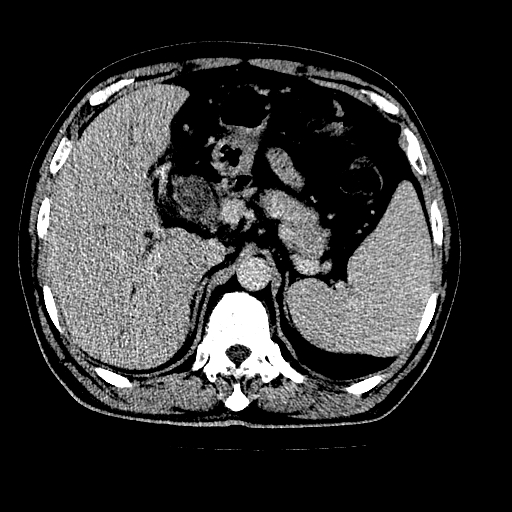

男,66岁,上腹部不适、黄染一周。彩超示:肝左叶占位,肝内胆管扩张,胆总管扩张,胆总管占位?

肝左叶不规则软组织肿块影,边缘不规整邻近肝实质受累分界不清;肝内胆管(左叶)明显扩张成“软藤状”,诊断:肝左叶胆管细胞癌。

肝左叶占位性病变,并胆管扩张,符合胆管细胞癌ct表现,门脉左支受累,左肾囊肿。窗宽太窄了,其他的看不清

左叶胆管细胞癌累及胆总管,门脉左支受侵,慢性胆囊炎胆结石,左肾小囊肿